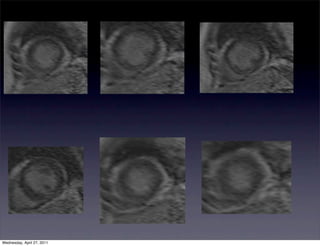

Dobutamine CMR

•       Contractile reserve can be assessed using low dose dobutamine stress test

•   Allows for superior endocardial border definition facilitating more

accurate wall motion and wall thickening

•       Dobutamine CMR vs PET

•   35 patients with mild LV dysfunction

•   Sensitivity of 88% and Specificity of 87% for detecting regions of viable

myocardium

•       Reduced predictive ability with more severe dysfunction is present at rest

with specificity in the 80% range, but sensitivity limited to 50%

•   If contractile function improves with dobutamine the there is likely

viability

•   Lack of improvement, however, does may not rule out viability as

ischemia may develop at even low levels of dobutamine administration

Mahrholdt, et al. Heart 2007